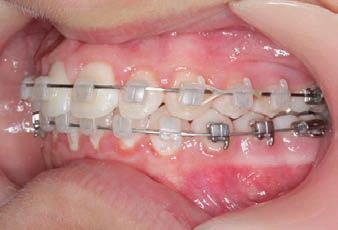

The SAGITTAL FIRST™ Philosophy is a time-tested approach that standardises, simplifies, and shortens Class II and Class III treatment times. It employs the Carriere Motion 3D Appliance to treat the AP dimension at the beginning of treatment before placing brackets or aligners. By resolving the most difficult part of treatment first, you can achieve a Class I platform in 3 to 6 months, shortening total treatment time by a minimum of 6 months1. You know how excited patients and parents become when you mention shorter treatment times.

CLASS II DIV.1 - Marra

INITIAL - 4/4/18

PROGRESS 1 - 26/9/18 - Class I platform accomplished in 5.75 months with Motion 3D COLOR Appliance

PROGRESS 2 - 26/9/18 - Placement of the SLX 3D Clear Brackets

with M-ONE .015 Cu Nitanium 27°

PROGRESS 3 - 30/10/18 - With M-TWO .020 x .020 Cu Nitanium 35° archwire

PROGRESS 4 - 27/11/18 - 3 links power chain: 5, 4, bypass 3 to crimp hooks

PROGRESS 5 - 13/3/19 - With M-TWO .020 x .020 Cu Nitanium 35° archwire

PROGRESS 6 - 1/8/19 - With M-THREE.019 x .025 Beta Titanium wire